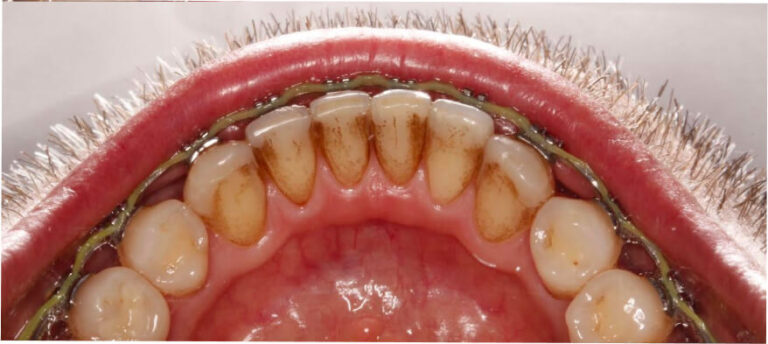

Po

Higienizacja